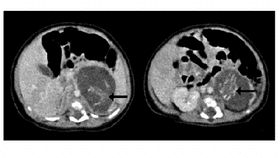

A few days later, the baby was given further ultrasound examinations and a CT scan, which revealed two solid masses, each possessing two long bones and a spine. The decision was therefore made to surgically remove the masses when the baby was just 14 days old.

Examination of the excised masses revealed two fetuses, each possessing an umbilical cord joined to a placenta-like structure. The tiny fetuses were believed to be around 10 weeks of age, measuring 37 mm and 35 mm in length and weighing just 14.2 g and 9.3 g. Despite being different sizes, the level of development was identical. They both possessed four limbs, segmented spines, well-developed rib cages, primitive brain tissue, intestines and an anus.